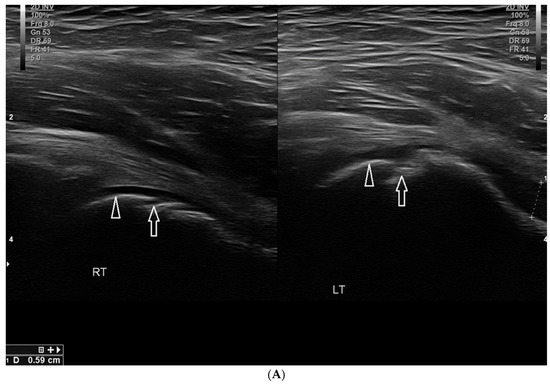

- Szczepaniak, J.; Ciszkowska-Łysoń, B.; Śmigielski, R.; Zdanowicz, U. Value of ultrasonography in assessment of recent injury of anterior talofibular ligament in children. J. Ultrason. 2015, 15, 259–266. [Google Scholar] [CrossRef]